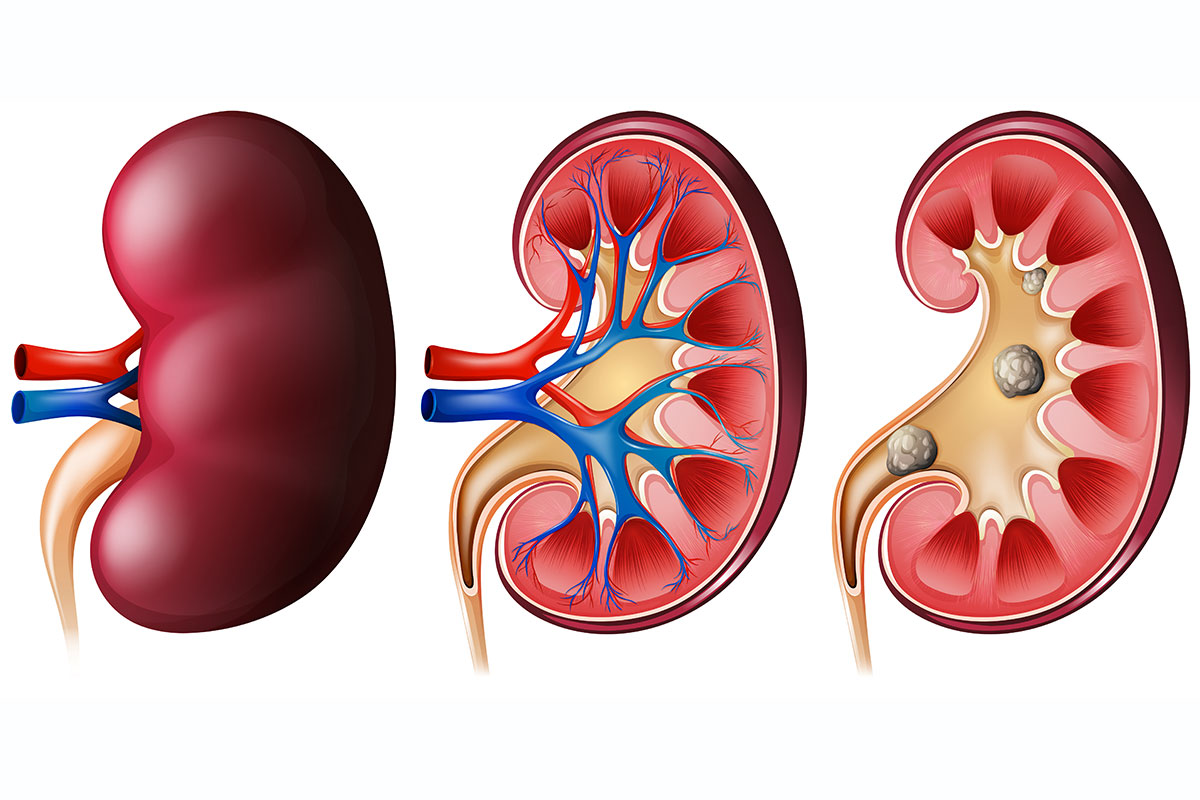

• Renal Stones

Renal Stones or Gall Stones, etc...